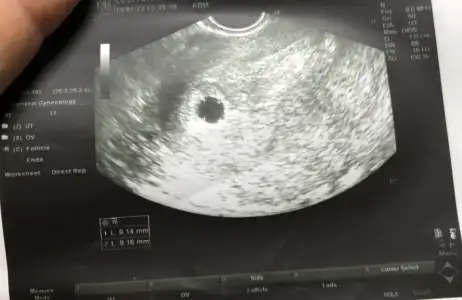

Merhaba kızlar pazartesi ultrasona girmiştim bebek görünmemişti dün lekelenme olunca tekrar gittim kese var ama kanama düşük tehlikesi olur dedi progestana devam dinlen ekledim ilk ultrasın ve 2 ultrasın keseleri bi bakrmısınıx kızlar kese içindeki beyazlar nedir acildeki doktor çok açıklama yapmadı sordum

• B0BA1324-BE4C-426A-AF5C-E8F58B831963.webp

B0BA1324-BE4C-426A-AF5C-E8F58B831963.webp

26,5 KB · Görüntüleme: 96

Ultrason prob hareketinden olan yansımalar onlar kaçıncı haftadasınız??